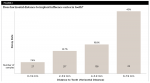

Implants used to replace molar teeth present issues of space distribution and crown contours that are unique to these sites. Because the diameter of the implant typically is smaller than that of the tooth being replaced, and the circular shape of the implant does not replicate the anatomy of the tooth, a large gingival embrasure area between the implant platform and adjacent tooth often results. Upon the review of radiographs of molar implants placed over an 11-year period in one private practice, the authors identified an unusually high incidence of approximal, cervical, and root caries on teeth adjacent to these implants. This retrospective radiographic study investigated the incidence of decay as related to: (1) the horizontal distance from the implant to the adjacent tooth (ie, the implant-tooth distance, or ITD) as measured at the alveolar crest, (2) the vertical distance from the apical portion of the prosthetic contact area to the implant platform, and (3) the presence of an existing restoration on the adjacent tooth. Of the three variables examined, both the horizontal distance of the implant to a natural tooth (ITD) and the presence of an existing restoration on an adjacent tooth proved to be significantly correlated with the incidence of decay. Results showed that incidence of decay ranges from 7.4% when the ITD is <2 mm to 40% when the ITD is ≥6 mm. The mean ITD in cases in which decay was found was 4.1 mm, and it was 3.5 mm in cases that showed no decay (P = .005). It is therefore suggested that the horizontal threshold of 4 mm be considered as the "critical ITD." The results also indicated that the presence of a previous restoration on an adjacent tooth increases the incidence of decay to a statistically significant degree with an odds ratio of 2.25 at a 95% confidence level. This information may prove useful in diagnosis and treatment planning for molar implant replacement.

Horizontal distance from the implant platform/abutment connection to the adjacent tooth: The data indicates that as the distance between the natural tooth and the implant increases, the incidence of decay increases precipitously (Figure 2 and Figure 3). Decay occurrences range from 7.4% when the implant-tooth distance (ITD) is <2 mm to 40% when the ITD is ≥6 mm. In the 69 sites that exhibited caries, the mean ITD was 4.1 mm, and in the 338 sites without decay the mean ITD was 3.5 mm (P = .005) (Table 1). A logistic regression was performed with the single binary variable indicating whether or not the "horizontal threshold distance" was greater than 4 mm. The results show a statistically significant odds ratio of 2.00 (95% confidence interval of 1.191599, 3.350288) (Table 2.) Therefore, it is suggested that the horizontal threshold of 4 mm be considered as the "critical ITD."